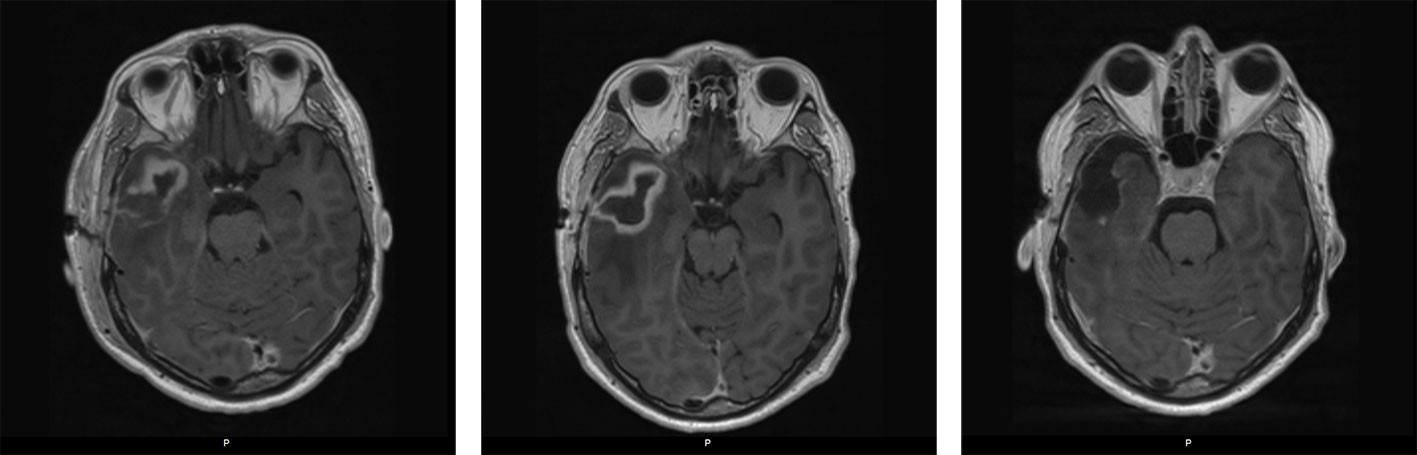

MR caput med intravenøs kontrast bekreftet funnet (figur 6). Han ble reoperert dagen etter i narkose med rekraniotomi og fjerning av abscess med kapsel. Pasienten kom seg raskt etter operasjonen uten nevrologiske utfall.

MR caput seks uker etter operasjonen viste ingen residiv. Tremånederskontroll hos nevrolog, infeksjonsmedisiner og kardiolog viste tilfredsstillende forhold.